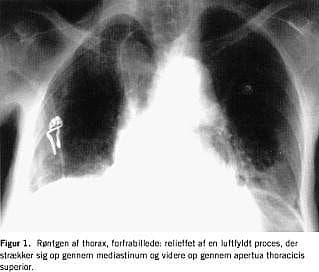

Blodtrykket var 220/120. Et elektrokardiogram (ekg) viste sinustakykardi, frekvens 134, uden tegn på iskæmi. Patientens saturation ved ankomsten var 92% på 8 l ilt pr. min. A-punktur viste svær respiratorisk acidose, pH=7,13. Røntgen af thorax viste en dilateret subdiafragmalt beliggende ventrikel og en dilateret colonslynge i mediastinum strækkende sig helt op i halsregionen, der sås normale lungefelter (Figur 1 og Figur 2 ).

I den foreliggende sygehistorie har der formodentlig været tale om herniering gennem hiatus oesophageus. Dette blev vurderet af en speciallæge i radiologi ud fra røntgen af thorax i to planer.